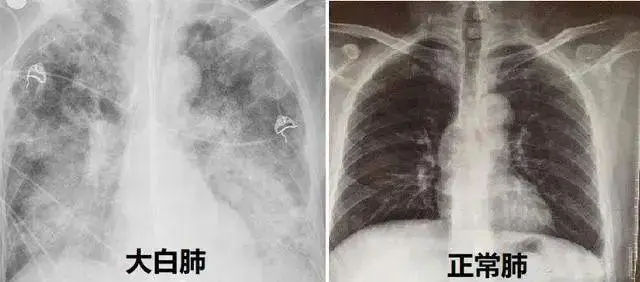

• "白肺" 2023-01-17

虽然有人说新冠奥密克戎只是"大号感冒",但是随着感染人数的持续增加,大多数人都出现了明显身体不适症状,这个说法也是不攻自破。大多数患者感染奥密克戎之后,主要还是以轻症为主,很多人在家自行服药治疗往往就能够得到缓解···